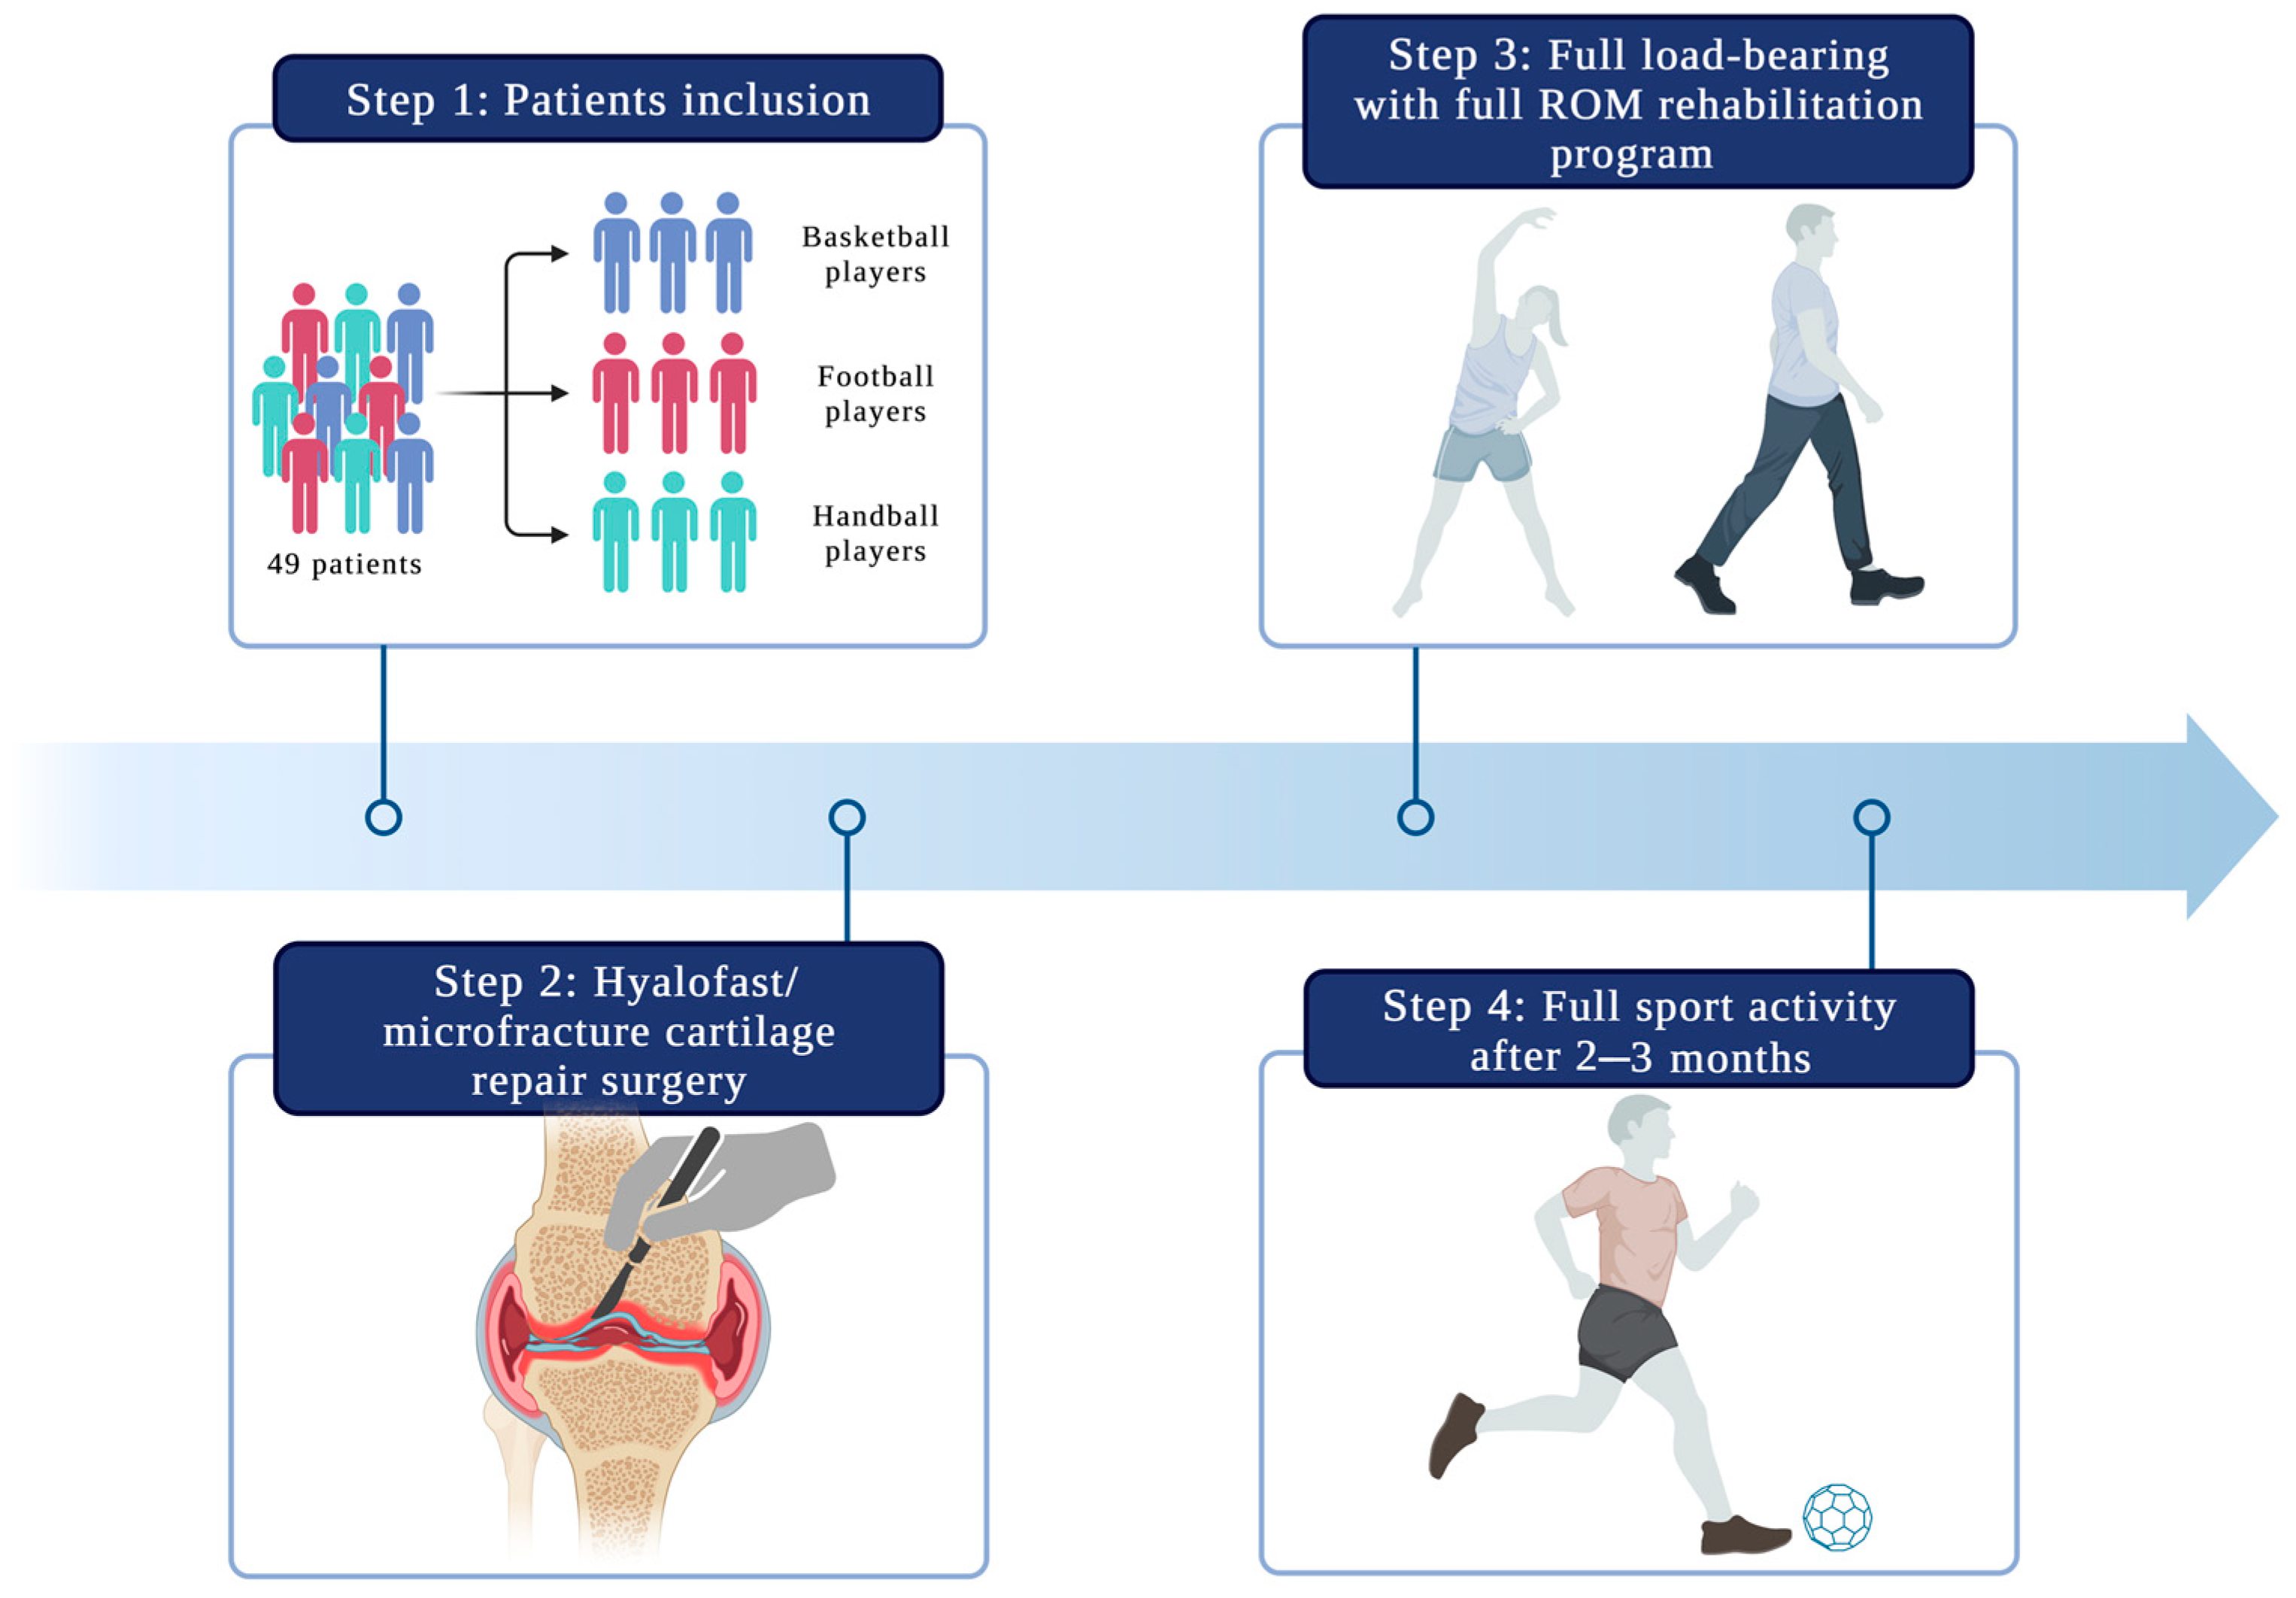

2. Materials and Methods

2.1. Patient Selection

2.2. Operation Procedure

2.4. Rehabilitation Protocol